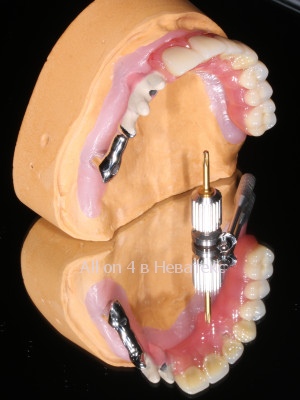

При изготовлении постоянного конструктива(начинки) протеза применяется технологичное литье MESA Magnum H50 с прессованием (Ti)титана 5 Grade. Отдельное и самое важное посещение пациента на 3 й день после операции - примерка гибридной балки гребнки, армирующей базу где распределяется пиковая нагрузка зубов - это и есть *скелет постоянной конструкции и основа привычных жевательных нагрузок.

Далее рассмотрим параметры введения протеза и что же все-таки такое балка и зачем она нужна. Самое важное условие при винтовой фиксации протеза к мультиюнит-аббатментам это его пассивное введение. Шахта титанового рукава в протезе должна четко и точно быть конгруэнтна шахте мультиюнит-абатмента. Введение болтика при винтовой фиксации и прикручивание протеза, не должно иметь внутреннего напряжения - дотяжка на 15 Н/см2 не должна иметь никаких боковых смещений. Также важно понимать, что на этом этапе, для успешного результата протез не дотягивается плотно к кости альвеолярного гребня, активно не дожимается, чтобы не было выталкивающего движения и негативного воздействия на незажившие имплантаты. Протез на первом этапе прилегает только к слизистой и функционирует на расстоянии зубной нити, между базой протеза и костными структурами гребня.

Керамокомпозито-наполненный диоксидом кремния протез на гибридной балке с титановой основой требует трех примерок после операции All-on-4 / All-on-6 и в отличии от металлопластмассовых адаптационных конструкций не требует перепротезирования

Литая балка в каркасе протеза армирована поясом на титановой основе, что значительно увеличивает прочность конструкции в целом.

Постоянный гибридный керамокомпозито-наполненный протез на ( балке-прототип Nobel Bar> включена в стоимость акции ), армирующей базу протеза, равномерно распределяет выламывающие горизонтальные тризмы, при переходе от адаптационных к постоянным нагрузкам, считается постоянной конструкцией для долгосрочного использования.

![]() |